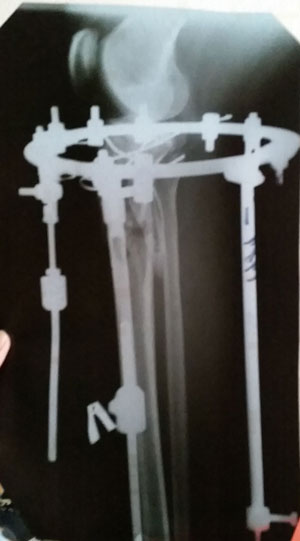

рентген в 90 дней с момента операции.

Ураа аЗдравствуйте, Ласка! По рентгену всё идёт хорошо, регенерат хороший, всё по плану. Через месяц будем готовиться к снятию аппаратов! (предварительно сделав рентген и выслав нам).